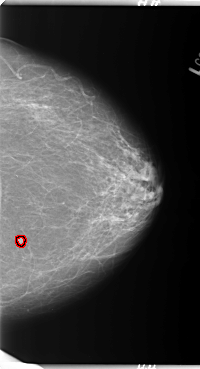

B_3089_1.LEFT_MLO

FILE: B_3089_1.LEFT_CC.OVERLAY

TOTAL_ABNORMALITIES 1

ABNORMALITY 1

LESION_TYPE MASS SHAPE ROUND MARGINS CIRCUMSCRIBED

ASSESSMENT 4

SUBTLETY 4

PATHOLOGY MALIGNANT

TOTAL_OUTLINES 1

BOUNDARY